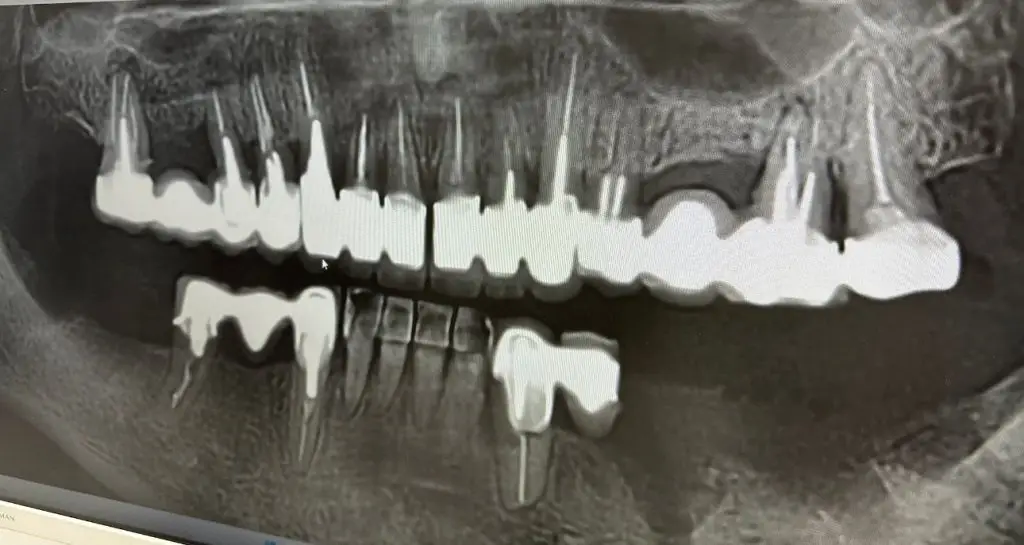

Pacienta a venit la clinica noastră pentru a-și îmbunătăți zâmbetul si pentru a scapa de infectiile repetate de sub lucrari.

Dintii de sub lucrari au fost irecuperabili, din cauza distructiei coroanei dar si a infectiei de la varful radacinii.

Am recomandat extractia dintilor, aditii osoase pe zonele laterale, sistemul all on 8 la maxilar, conservarea dintilor frontali mandibulari si implanturi in zonele laterale mandibulare.

All on 8 maxilar cu inserarea lucrarii provizorii, intraorale, a 2 zi, postoperator

Implanturi pe zonele laterale mandibulare

Dupa osteointegrarea implanturilor, s-au realuzat lucrarile finale din ceramica stratificata pe zirconiu, atat la maxilar cat si la mandibula.